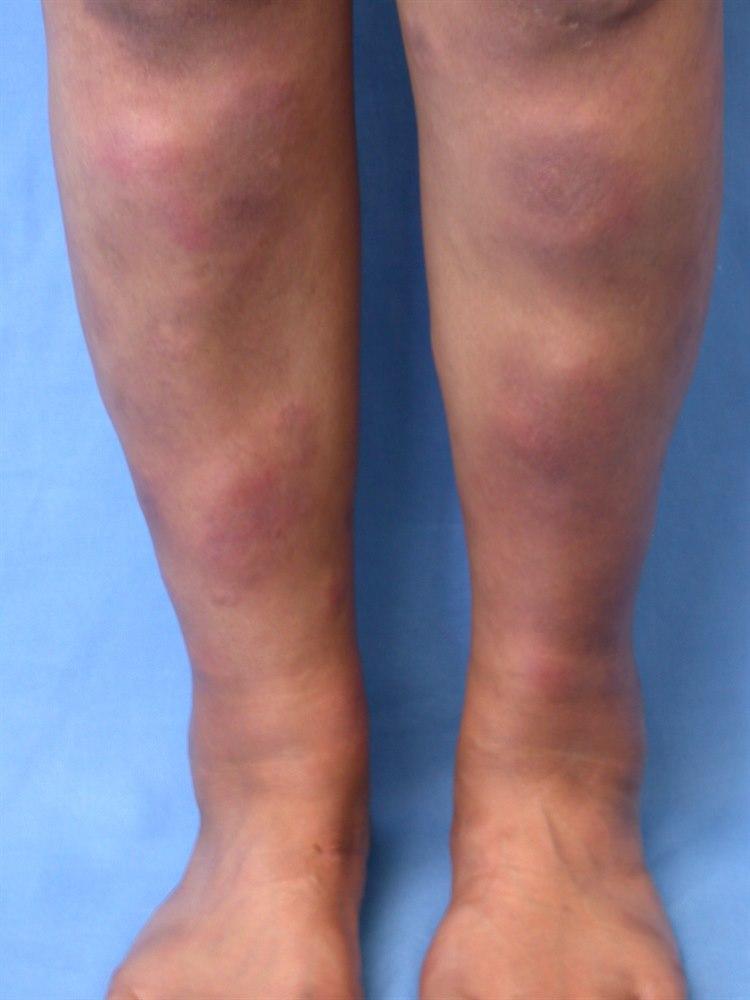

Erythema nodosum (knuterosen) er en akutt betennelse (inflammasjon) i underhudsfettet (pannikulitt). Tilstanden viser seg i starten som en hevelse med røde knuter som er svært følsomme for trykk. De fleste knutene er lokalisert symmetrisk på forsiden av leggene.

Tilstanden starter gjerne med ømme utslett på leggene. I noen tilfeller har det på forhånd vært en periode med feber, slapphet og leddsmerter. Erythema nodosum-knuter varierer fra en til ti centimeter i diameter. Knuter på forsiden av leggene er vanligst, men de kan også forekomme på strekkeflatene på underarmene, lårene og kroppen. Den første uken er knutene faste og ømme, men blir etter hvert mykere og mindre ømme.

Enkeltstående knuter består i cirka to uker, mens nye knuter kan fortsette å komme i opptil seks uker. Det kan ta cirka en til to måneder, noen ganger helt opp til 6 måneder, før knutene forsvinner fullstendig. Fargen på knutene endrer seg fra høyrød til rødfiolett og rødbrun, og i sluttfasen ser knutene ofte ut som bloduttredelser. Knutene omdannes ikke til sår, og de går vanligvis tilbake uten å etterlate seg skadet hud eller arrvev.